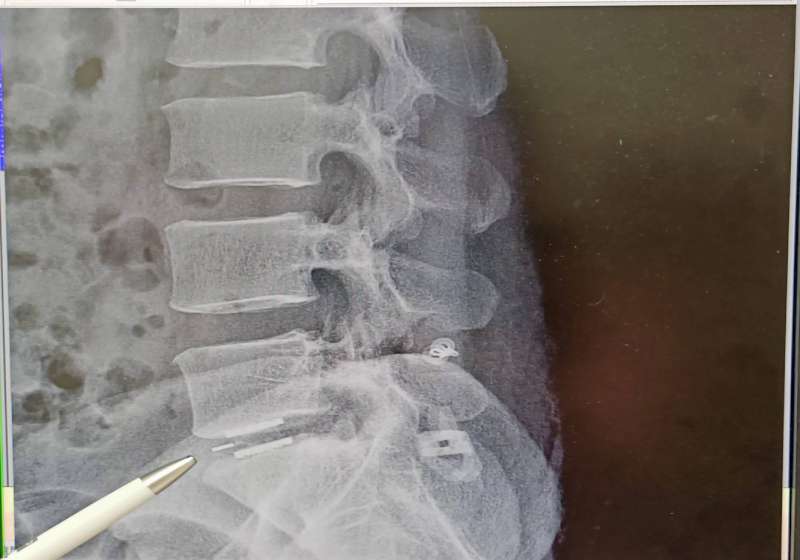

屏東市31歲男子因農務需搬重物,112年左側腰臀疼痛延伸腳踝,影響正常生活,經核磁共振檢查確認第五腰椎及第一薦椎神經壓迫,上網獲知七賢脊椎外科醫院副院長朱晟瑋病友手術成功經驗,決定來高求醫,接受無鋼釘穩定器微創手術治療,術後隔天獲得明顯改善,一週正常步行,感謝妻子悉心照料。

朱晟瑋說,臨床常見腰椎及薦椎神經壓迫肇因長期姿勢不良,無鋼釘穩定器微創術兼具安全性高、復原快等特性。 圖/七賢脊椎外科醫院提供、文/高培德